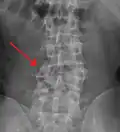

A burst fracture of L4 as seen on CT -

A burst fracture of L4 as seen on CT